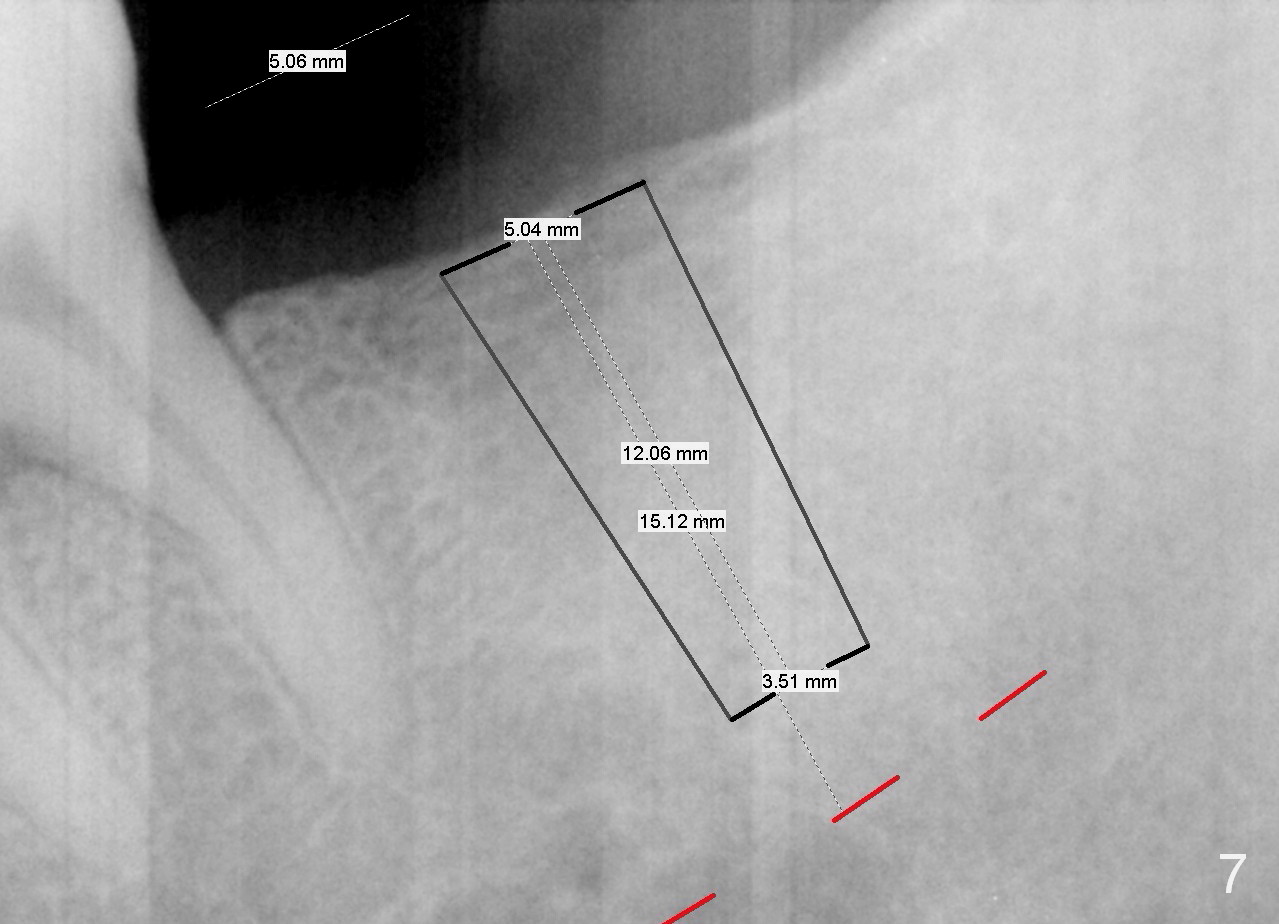

A 51-year-old man has lost #18 for more than 10 years (Fig.1,6). There appears to be sufficient bone height for implant (15 mm (Fig.7 (red dashed line: the superior border of the Inferior Alveolar Canal))). Prepare 4 mm implant spacer and SM starter drill and 2 mm pilot drill at 12 mm. Take PA. Palpation reveals that the edentulous ridge is wide. Place an implant in the middle of the ridge (buccolingually).

On second thought, Bicon implant is to be placed, either 4.5x8 or 5x6 mm (Fig.8).